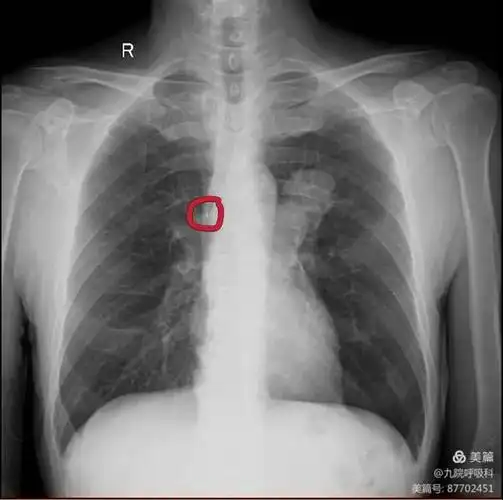

晚期肺癌的长期生存在坚持与关爱中实现

右侧中心型肺癌,右肺切除术后两年,术后残腔?——中心医院病例库

支气管肺癌怎么读片看看不同类型的支气管肺癌影像诊断